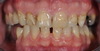

Restaurations par couronnes céramo-céramiques

Couronnes céramiques sur incisives latérales et facettes sur incisives centrales